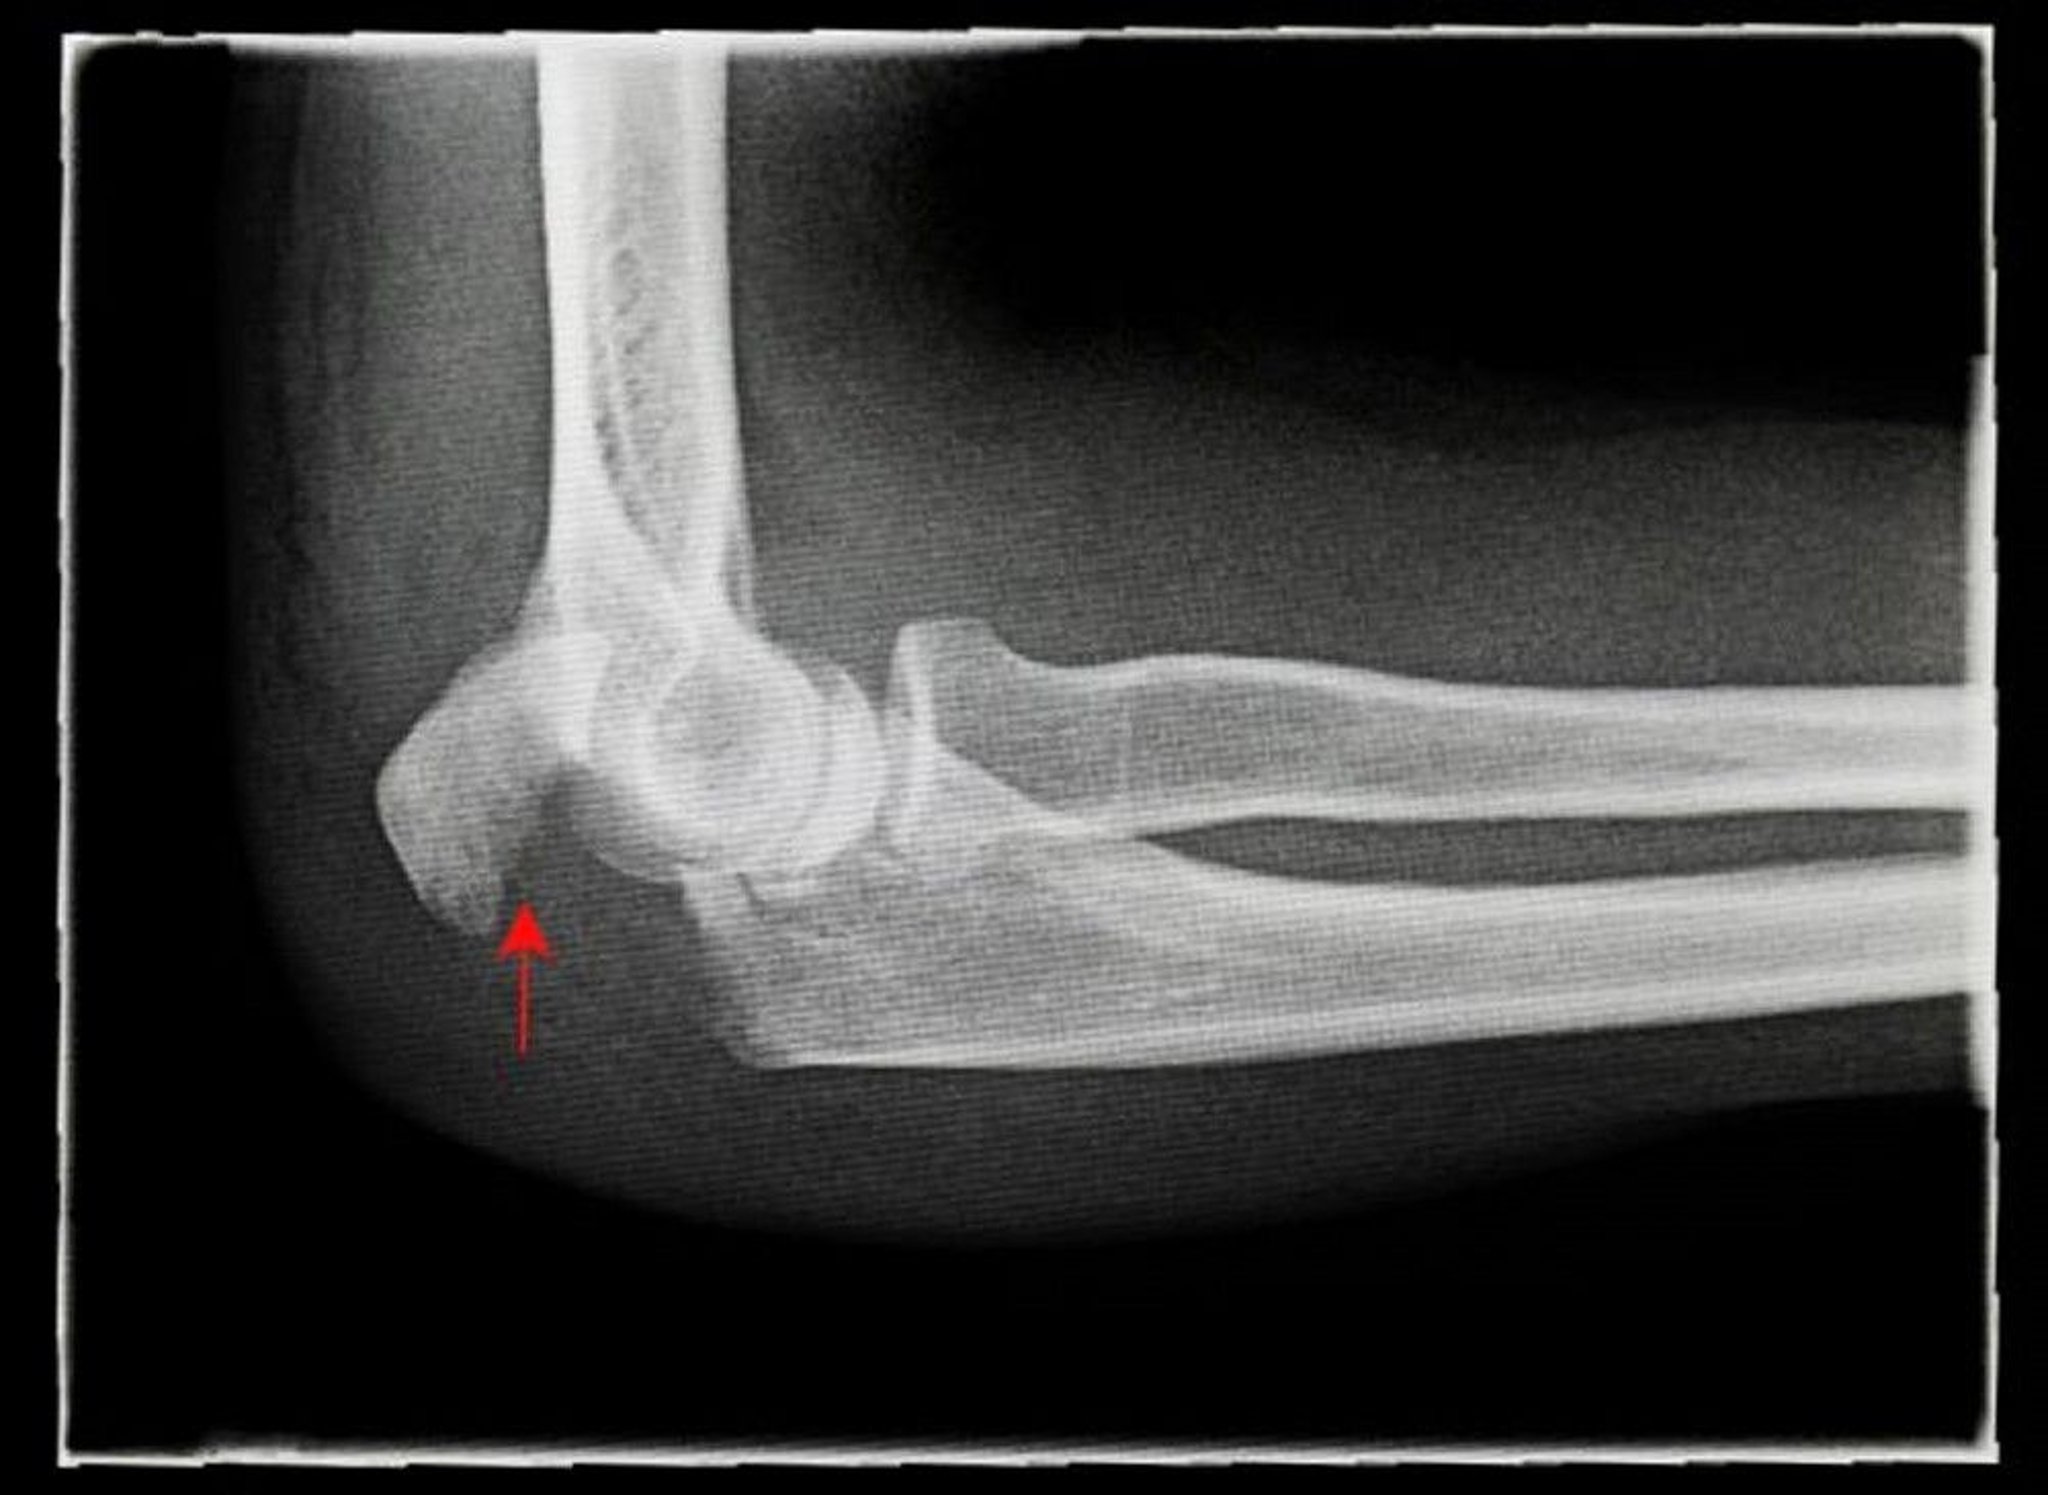

尺骨神経が損傷を受ける可能性があるため,末梢の神経血管の診察が極めて重要である。肘関節の標準的な前後像および側面像で大半の骨折が明らかになり,側面像で最も顕著である。

肘頭骨折

Credit line: ANTONIA REEVE/SCIENCE PHOTO LIBRARY